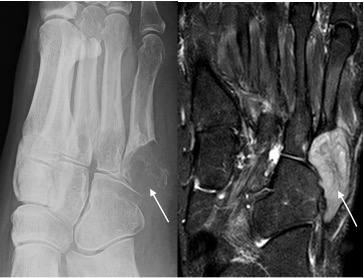

Metastases

- Needs to be considered in the differential diagnosis of any lytic lesion in a patient >40 years

- Metastases to the foot are most commonly from primary lung carcinoma

- Usually lytic, destructive lesions

- Sclerotic lesions most commonly prostate and breast metastases

- Thyroid and renal metastases produce expansile lesions

Metastasis base 5th metatarsal seen as lytic destructive lesion (arrow) in patient with known lung carcinoma